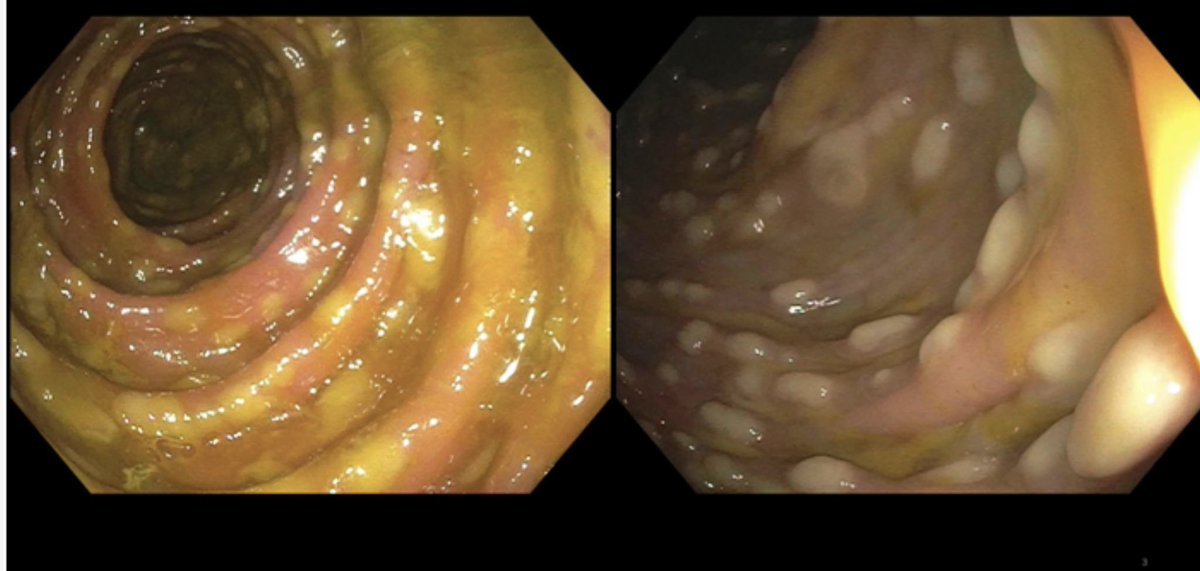

We are so excited to launch @Gisim_website • A free #Gastroenterology #Hepatology Interactive Case Based learning and teaching tool • #Meded #FOAMed Thank you @BhavanaBRaoMD @ssfarouk @Neph_SIM and all other collaborators • Check us out at GI-sim.com